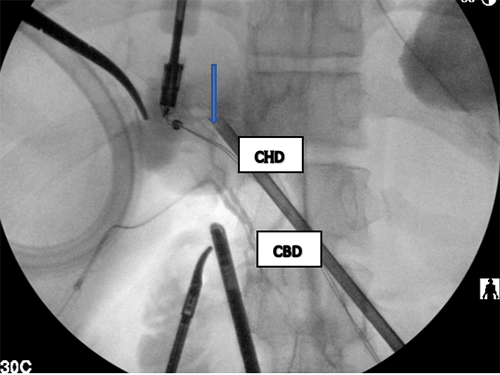

He did not have epigastric or right upper quadrant pain recurrence after his initial emergency room visitation. The patient was evaluated in pediatric surgery clinic and underwent a right upper quadrant ultrasound to attempt further delineation of the cyst. The ultrasound demonstrated a 3.6 cm cystic lesion abutting or within segment IV, also noted to contain several gallstones (Figure 2). The patient was diagnosed with a choledochal cyst, likely type I based on imaging and was deemed appropriate for elective minimally invasive excision of the cyst with plans for bilioenteric reconstruction.

Figure 2. Ultrasound Demonstrating Gallbladder and Choledochal Cyst Containing Gallstones. Published with Permission